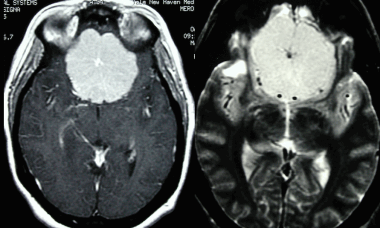

Фалькс-менингиома на МРТ.

А: на Т1-взвешенном МР-изображении отмечается солидное образование, характеризующееся изоинтенсивностью по отношению к твердой мозговой оболочке, инвазией в кость и сдавлением теменных зон коры.

В: На Т1-взвешенном МР-изображении с контрастным усилением видна частично контрастируемая опухоль.

С: На корональном Т2-взвешенном изображении видно изоинтенсивное образование, что соответствует плотной ткани. Такая картина характерна для фибробластных менингиом.

D : На Т1-взвешенном МР-изображении с контрастным усилением визуализируется гиперинтенсивное образование внутри мозгового вещества кости.